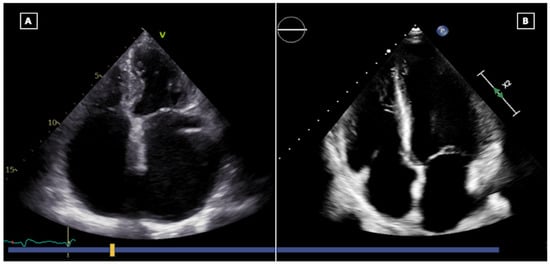

2.3. Evaluation of Postoperative Valvular Function

6. Echocardiography during Endomyocardial Biopsy